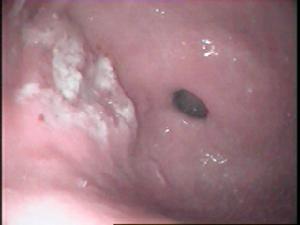

胃息肉胃息肉很少有陽性體徵,合併炎症時上腹部可有壓痛,出血多者有繼發性貧血表現。X線胃鋇餐透視和胃鏡檢查是診斷胃息肉的主要方法。X線胃鋇餐透視顯示胃腔內呈現圓形或半圓形邊界整齊清晰,表面平整的充盈缺損,多數在1cm左右大小,有蒂者可見其移動。胃鏡檢查對診斷實屬必要,鏡下可見胃壁黏膜上有圓形或半圓形隆,一般小於2cm。邊界清晰,表面光滑平整,色澤呈正常黏膜象或呈鮮紅色,質地柔軟,有蒂或無蒂,單發或多發。部分息肉呈菜花狀表現,其表面或有糜爛或有潰瘍。菜花狀息肉和體積大於2cm者有惡變之可能,活組織病理檢查有助於鑑別診斷。

而胃息肉與胃癌有很多的相似性,在診斷治療的時候切不可相提並論,息肉發生炎症時與胃炎表現相似。